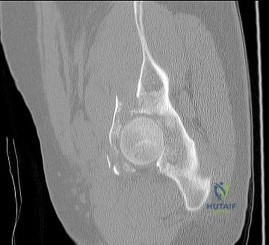

Question 40

A 45-year-old male is struck by a vehicle and sustains the injury shown in the reference radiograph.

The imaging confirms a highly depressed, isolated medial tibial plateau fracture (Schatzker IV) with a varus deformity. Which of the following surgical approaches and fixation strategies is most appropriate?

Explanation